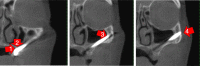

Results: The lack of maxillary boney support at the implant platform resulted in significant higher stress measured within the zygoma implant as well as the zygoma bone.

Conclusion: The maxilla is the primary support when zygoma implants are placed under functional loads. Quad-cortical stabilization of the zygoma implants and their cross-arch stabilization are recommended to reduce the degree of stress whenever possible.